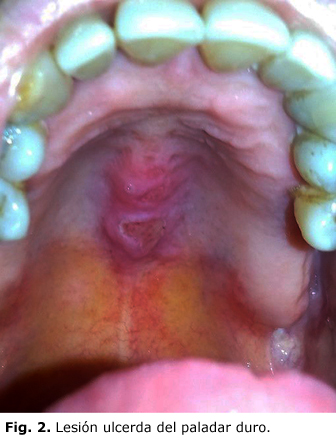

Paciente femenina de 64 años de edad, con antecedentes patológicos personales de hipertensión arterial desde hace 10 años, tratamiento con clortalidona, 1 tableta diaria y compensada de su enfermedad; comenzó hace 8 años con sensación de plenitud gástrica y meteorismo, con atención y seguimiento por su área de salud, sin mejoría de los síntomas, mantenidos en el tiempo hasta el último mes que comienza con diarreas en número de 2-3 deposiciones diarias, semilíquidas, en ocasiones después de la ingestión de alimentos, sin flemas ni sangre, amarillentas y no muy abundantes en cantidad, acompañadas de cólicos en algún momento. En los últimos 15 días aparece cansancio en las piernas y decaimiento, razón por la cual se decide su ingreso; evolutivamente en las siguientes 3 semanas después de su admisión aparecen lesiones ulceradas en región perianal (Fig. 1) y en la cavidad oral (Fig. 2 y 3), aumento de la frecuencia de las deposiciones llegando a presentar entre 8-10 diarias con iguales características, incluso en las noches, donde interfieren con el sueño.

Examen Físico: piel y mucosas con palidez cutáneo mucosa generalizada; lesiones ulceradas en región perianal de 0,5-1cm de diámetro, de forma oval y circulares, fondo limpio, dolorosas; lesiones similares en cara lateral de la lengua, paladar duro y labios. Sistema cardiovascular: ruidos cardíacos rítmicos y de buen tono, no soplos FC= 87 latidos por min. TA: 125/72 mm/Hg. Abdomen: blando, depresible, no doloroso a la palpación superficial, ni profunda, ruidos hidroaéreos normales. Hemolifopoyético: no adenopatías, matidez en el área esplénica del noveno al onceno espacio intercostal, que se extiende en el plano anterior hasta la línea medio clavicular.